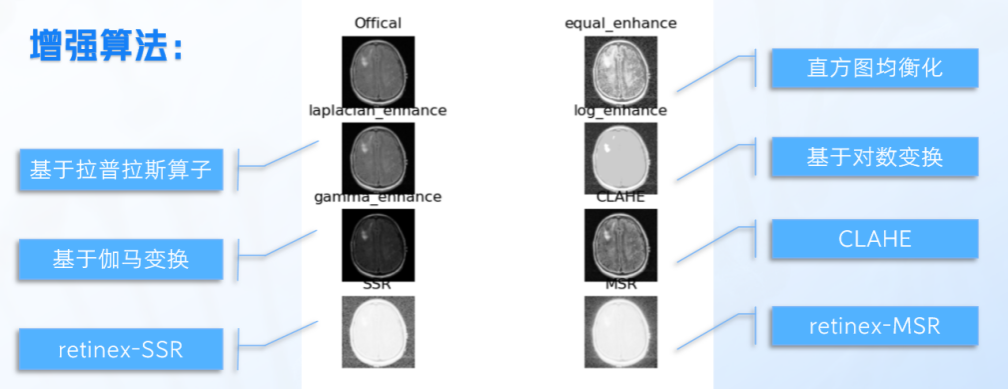

二、使用七种图像增强算法,选取效果最好的算法应用于模型训练预处理,改善图像的特征,使得分割算法更容易、更准确地识别和分离目标。